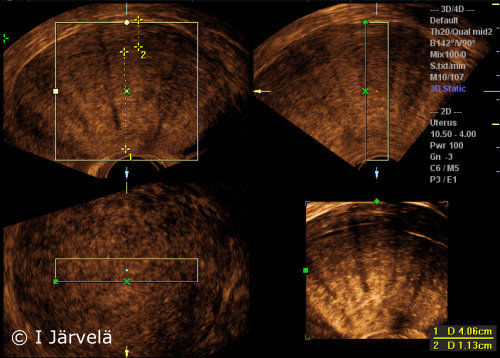

Adenomyosis (ultrasound scan). Note the disparity of uterine wall thicknesses and the inhomogeneity of myometrial echo.

Picture: Ilkka Järvelä; text: Dimitrios Scordas